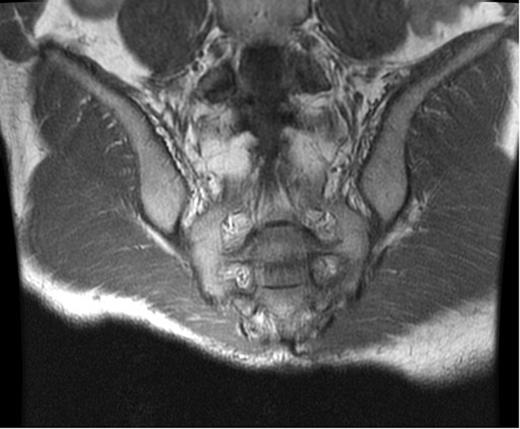

At the time of evaluation at our institution, he was afebrile and the laboratory tests, including inflammatory markers, were unremarkable. A computed tomography (CT) scan of the abdomen and pelvis showed a presacral fluid collection with a fistula between the pouch and the sacrum (Fig. 1). An MRI of the pelvis was performed and this revealed signs of osteomyelitis involving the S2–S4 vertebrae (Fig. 2). A laparotomy was performed and the ileal-anal pouch anastomosis was taken down, the sacrum was debrided leaving a large anterior bony defect. No omentum was available, so a 10 cm × 10 cm piece of Alloderm was used to cover the defect. The pouch fistula was excised and closed and the revised pouch re-anastomosed to the anus. The patient made an uneventful recovery and was discharged on the seventh postoperative day. Cultures from the sacral debrided tissue yielded Actinomyces spp. and a 12-week course of antibiotics (clindamycin) was commenced.